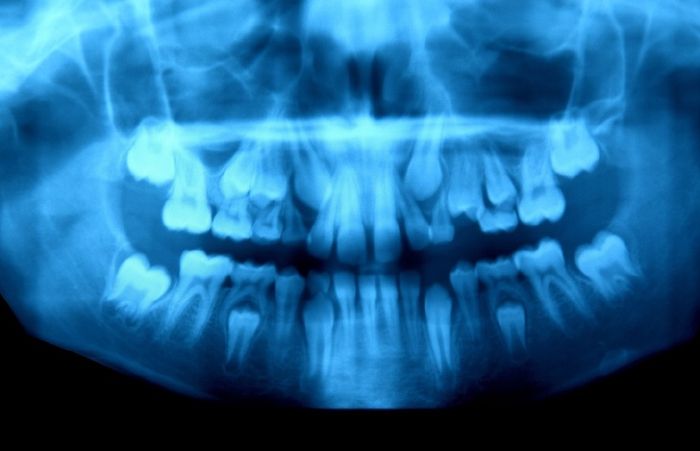

2. Egy 10 éves kisfiú állkapcsa, aki épp fogváltáson megy keresztül